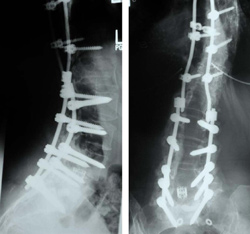

With spinal scoliosis surgery the surgical team will either create an incision in the patient's back, or in their front. If they are working from the front they will also have to deflate a lung in order to gain proper access to the spine. The surgery involves placing rods that help straighten the spine; in some instances this will also be grafting involving bone from other parts of the body. If the patient is still young the surgical team may use growing rods which can be altered as the individual's spine grows.